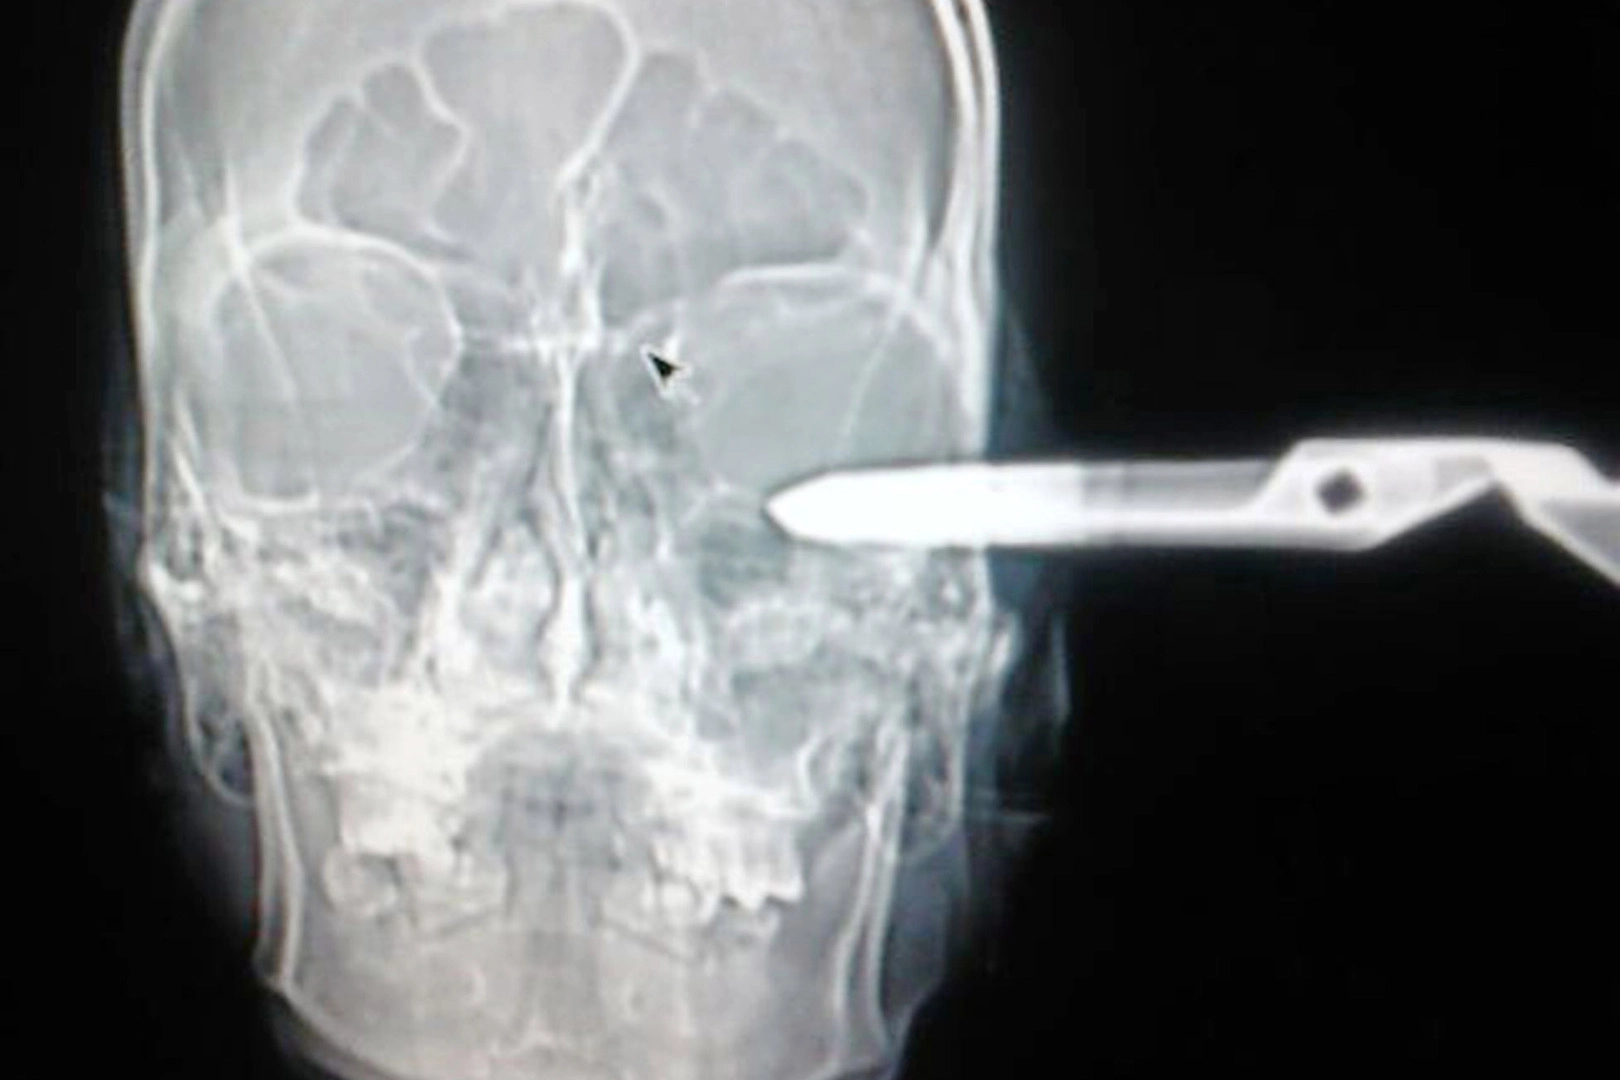

Мексиканец пришел в больницу с садовыми ножницами в голове

После медики сообщили, что мексиканцу повезло, что он остался жив, так как ножницы едва не повредили теменную часть мозга.